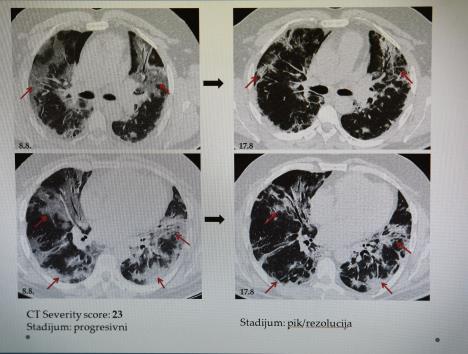

On dodaje da postoje četiri faze kroz koje prolaze pluća pacijenta s kovidom 19, a da na skeneru skor ide od 0 do 25, koji je i najgori i smrtonosan.

- Najpre ide takozvano mlečno staklo, kada se najmanji delovi pluća pune tečnošću, a što ne može da se vidi na rendgenu. Onda se pluća popločavaju, što vodi ka zapaljenju, i dolazimo do treće faze - konsolidacije, koja je i vrhunac bolesti, gde je pneumonija, najčešće obostrana, u punom jeku. To je neki 11-12. dan bolesti i nakon toga ili spasemo pacijenta ili, nažalost, sledi ARDS - akutni respiratorni distres sindrom, koji se završava fatalno - objašnjava dr Lalošević. On nam je pokazao snimak pluća pacijenta sa skorom 25, koji je preminuo na respiratoru, kao i pacijenta koji je takođe imao katastrofalan skor - 23, a uspeo je da se izvuče.

FAZE NAPADA KORONE NA PLUĆA

1. MLEČNO STAKLO 4-5. dan od početka bolesti. Acinusi - najmanji delovi pluća, pune se tečnošću i ona gube svoju funkciju

2. POPLOČAVANJE 8-10. dan od početka bolesti. Vodi ka pravom zapaljenju pluća, koje se tek vidi na rendgenu (mlečno staklo se ne vidi na rendgenu), vide se razni izlivi na plućima

3. KONSOLIDACIJA 11-12. dan bolesti. Pravo zapaljenje pluća i sam vrhunac bolesti. Iz ove faze se ide na ovu ili onu stranu, sledi ili oporavak ili smrtni ishod

4. REZOLUCIJA - faza kod onih koji prežive i idu ka oporavku. Stvaraju se tzv. fibrozne trake, ožiljavanje, gde se jasno vide ožiljci ostali od bolesti, ali i znak da sledi oporavak